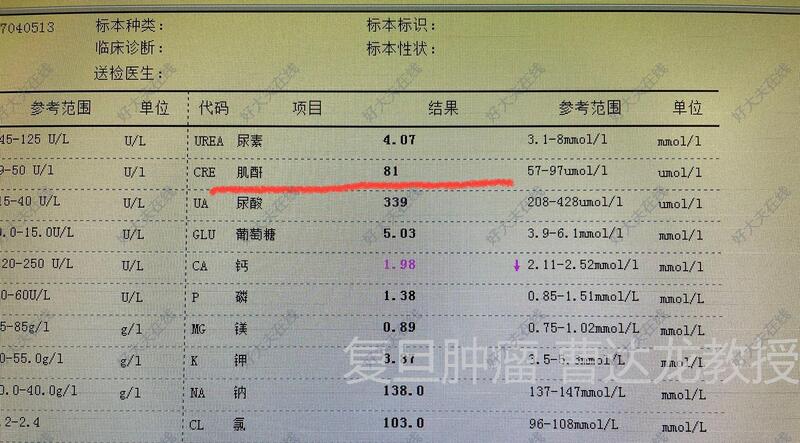

- 治疗后1天

术后恢复顺利,肾功能等指标均正常!